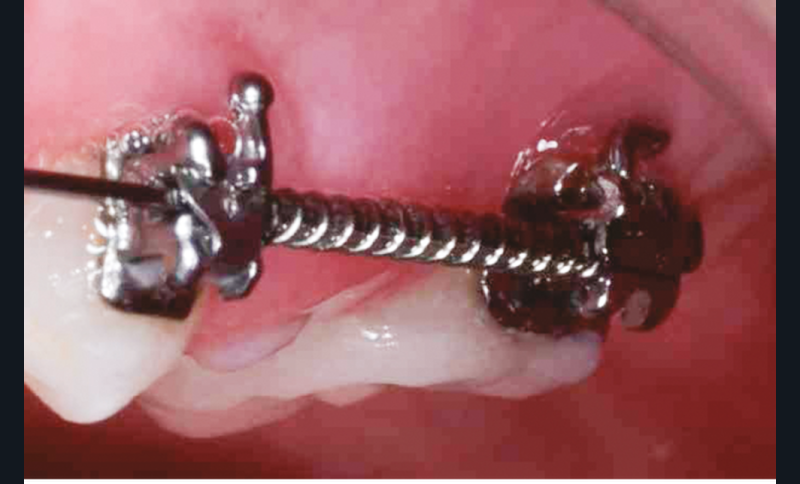

Le protocole de préparation de la dent ainsi que celui concernant l’assemblage de l’overlay céramique (fig. 2 à 7) suivent une séquence clinique habituelle [7, 8], à l’exception de deux étapes. Nous proposons ici, à la suite de l’éviction carieuse, d’intensifier la désinfection par l’utilisation d’O3 (fig. 3). Aussi, il nous paraissait intéressant, une fois la préparation prothétique effectuée, d’infiltrer cet « émail MIH » afin de potentialiser le collage et renforcer ses propriétés mécaniques ; l’infiltration résineuse agirait à l’échelle de l’émail comme le scellement dentinaire immédiat agit à l’échelle de la dentine (fig. 5). Une désinfection optimisée, un bandeau d’émail renforcé et le choix d’une restauration minimalement invasive qu’est l’overlay conduisent à un pronostic plus favorable pour l’avenir de cette dent, d’ailleurs incluse par la suite dans un traitement orthodontique (fig. 8).